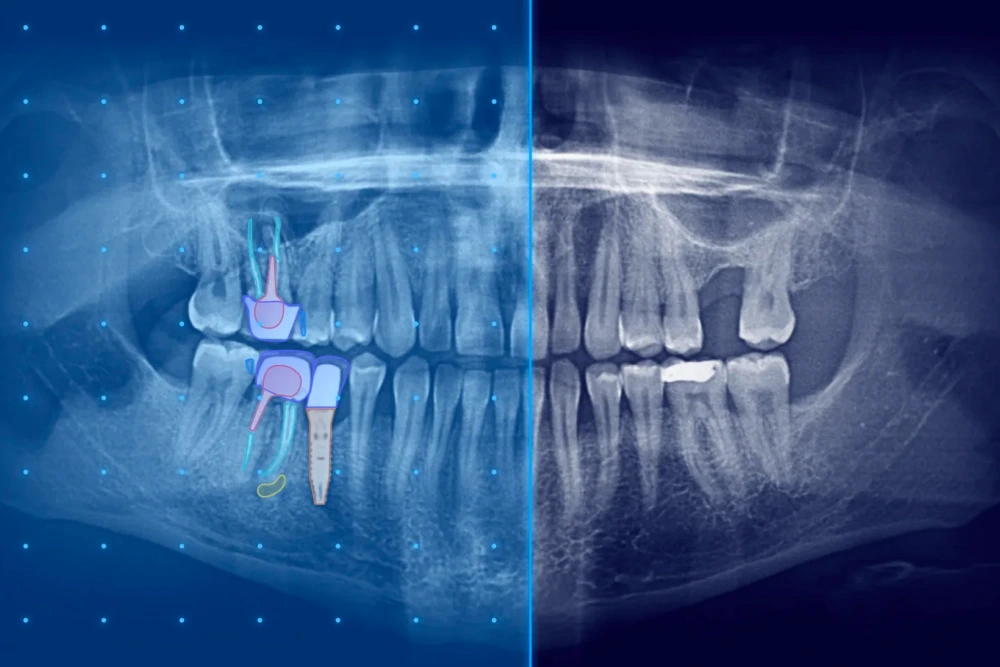

Analyse radiographique assistée par intelligence artificielle

IA en radiographie

L’intégration de l’intelligence artificielle en radiographie marque une avancée majeure en matière de diagnostics dentaires précis chez MLV Sourire.

Grâce à des algorithmes d’intelligence artificielle sophistiqués, ce système analyse les radiographies avec une précision exceptionnelle, détectant efficacement les détails anatomiques et les anomalies.